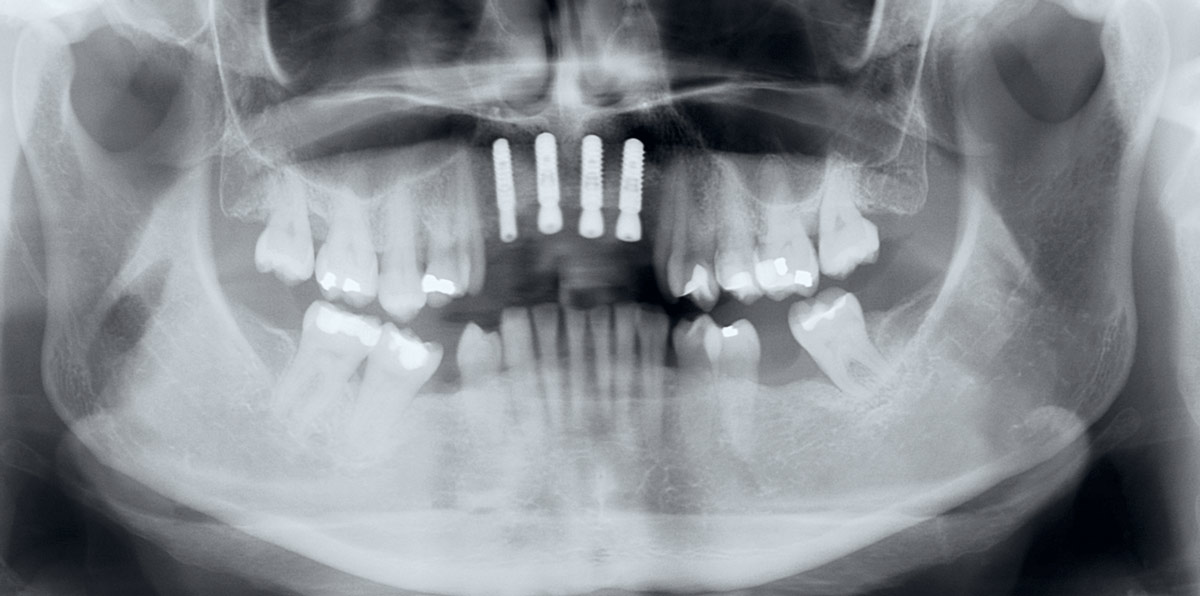

4/17 - X-ray scan after extraction of failing implantsRestoration of all four incisors with maxgraft® bonebuilder - Dr. Dr. Dr. O. Blume